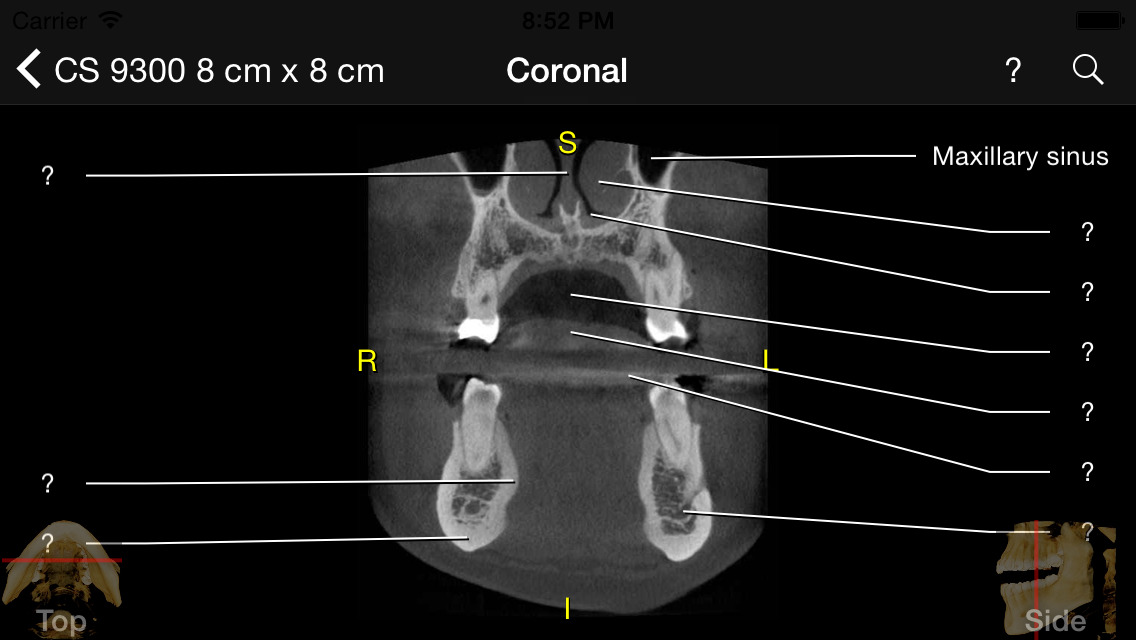

App Shopper CBCT (Medical) Cbct Medical Abbreviation Cbct, or cone beam computed tomography, is a type of technology and diagnostic tool that has revolutionized the way various scanning protocols are used. These new machines have some key differences from traditional. This drastic difference in radiation exposure underscores the importance of cbct technology in minimizing radiation exposure for patients. Initially, medical computed tomography (ct) was used for 3d. Cbct Medical Abbreviation.